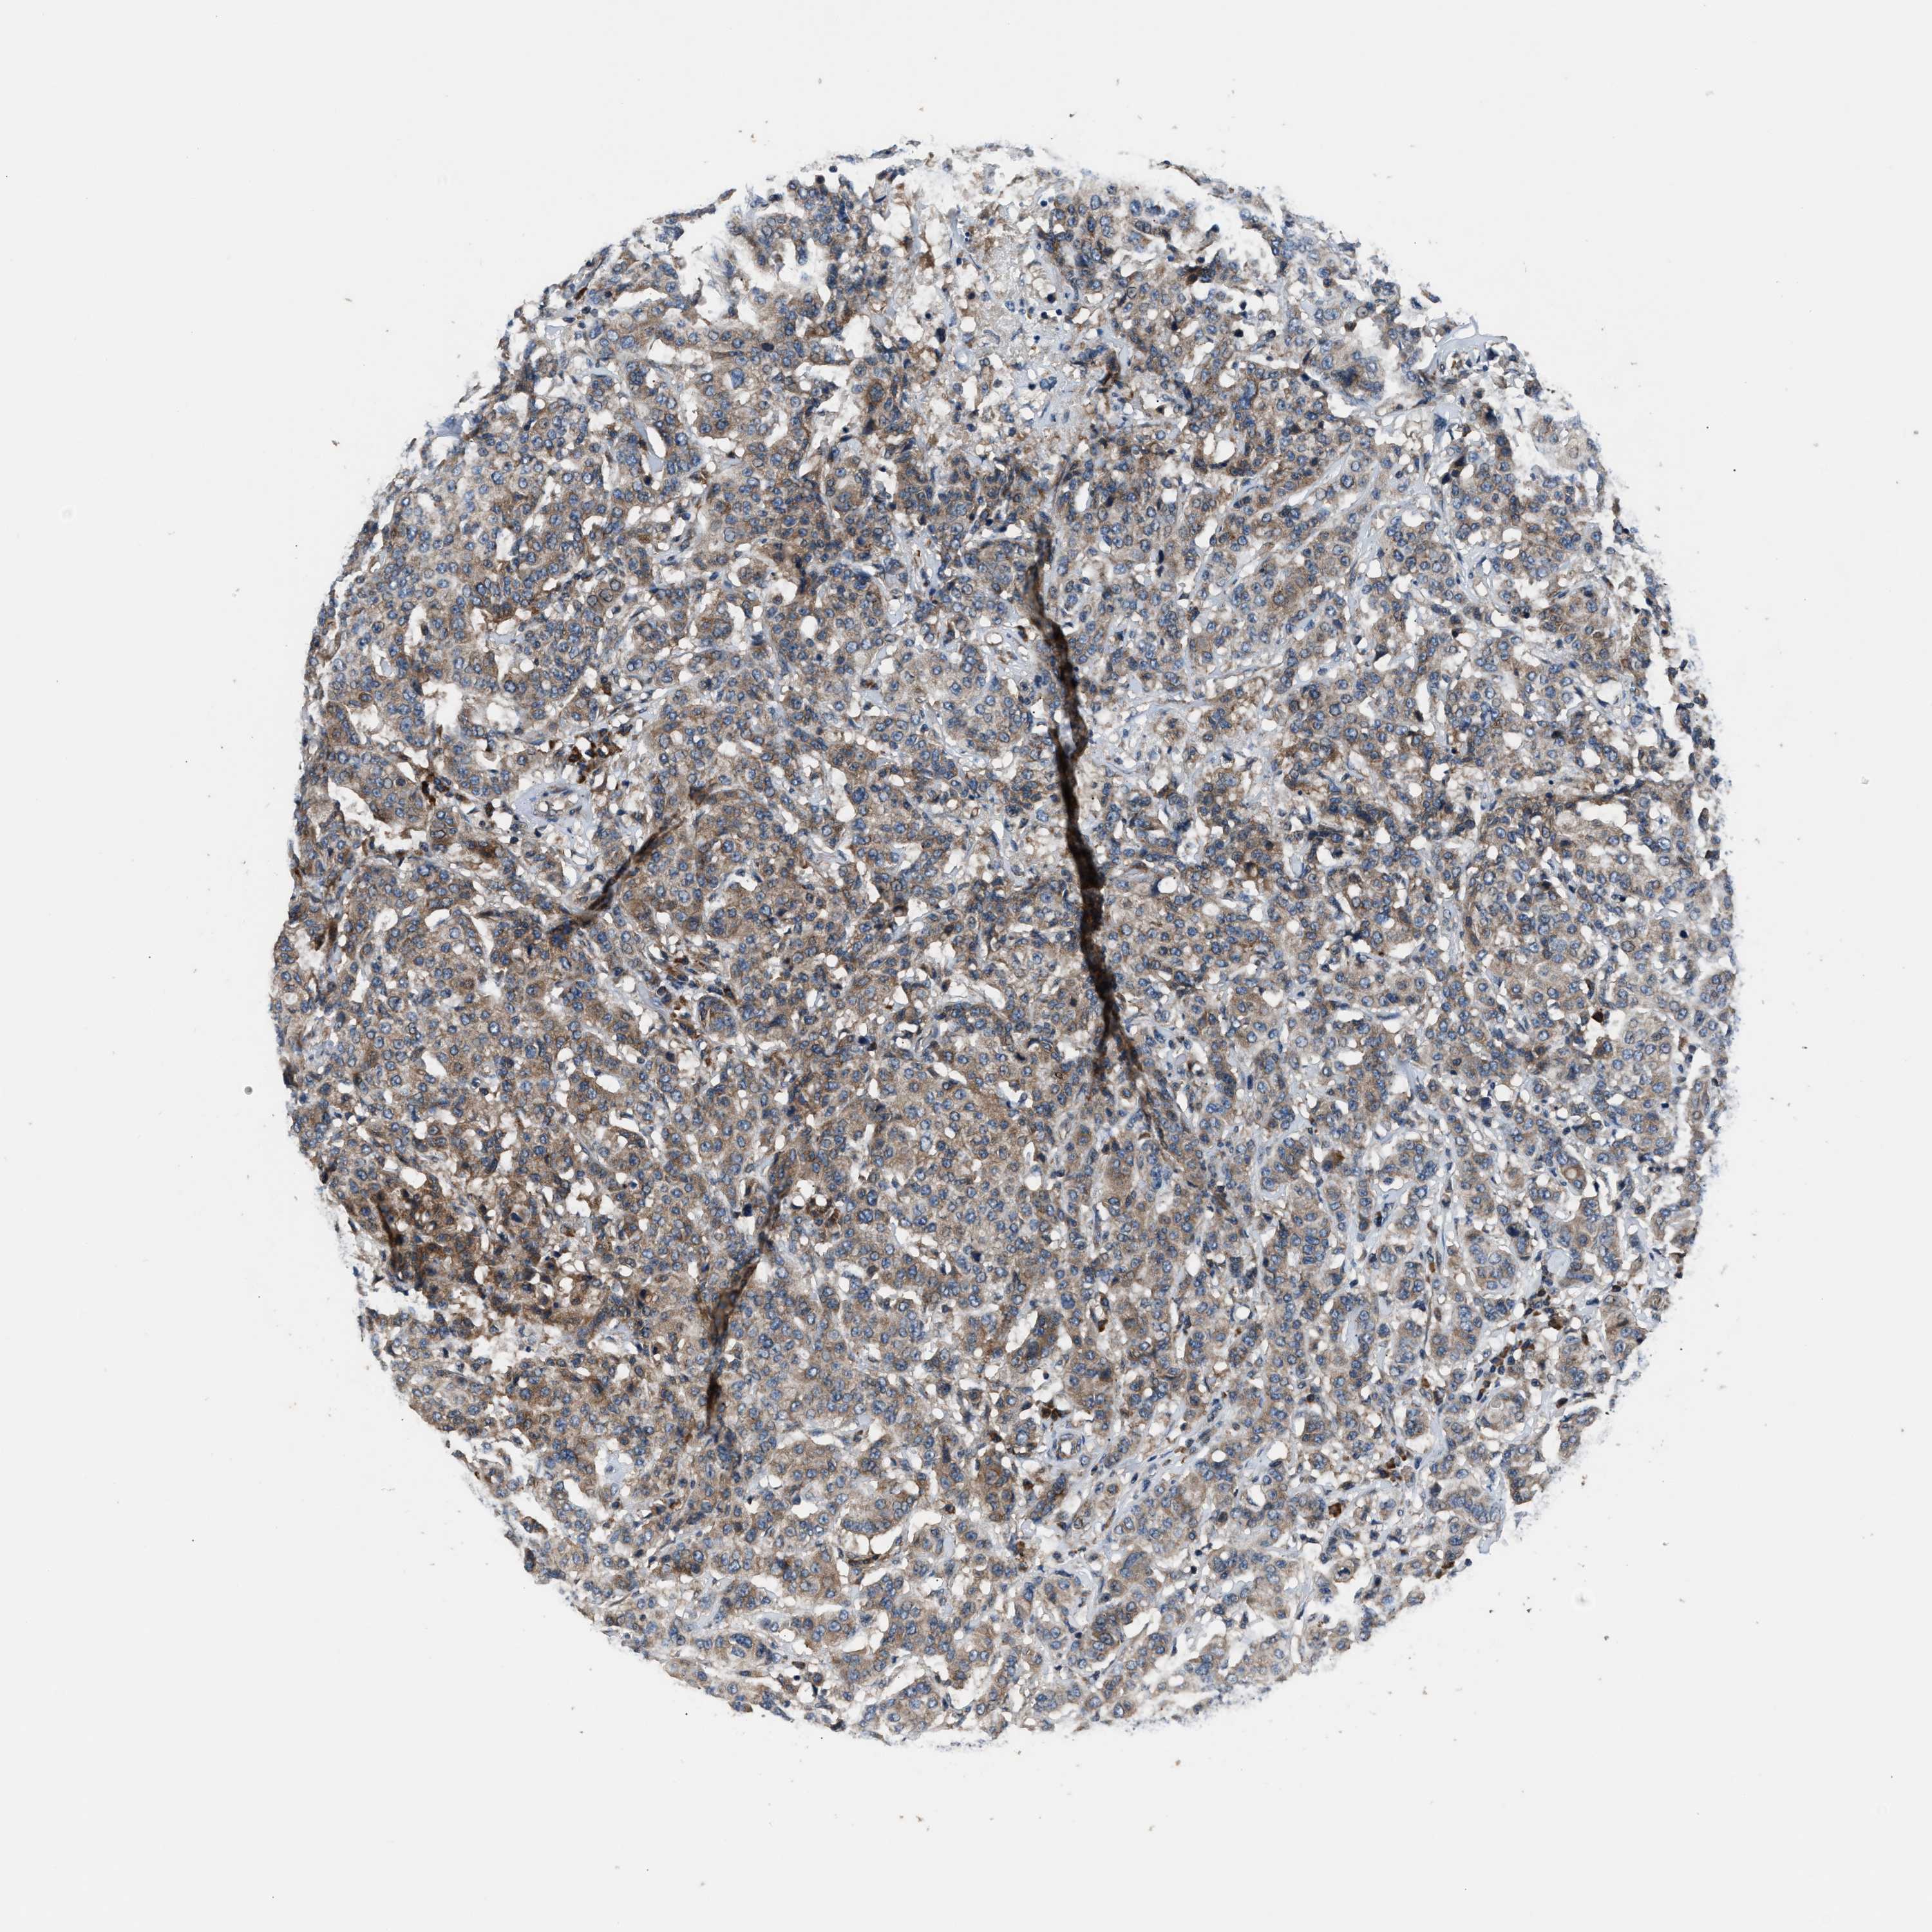

CANCER BREAST CANCER Show tissue menu

BRCA TCGA BRCA VALIDATION PROTEIN EXPRESSION

Breast cancer

Human cancer

Breast invasive carcinoma